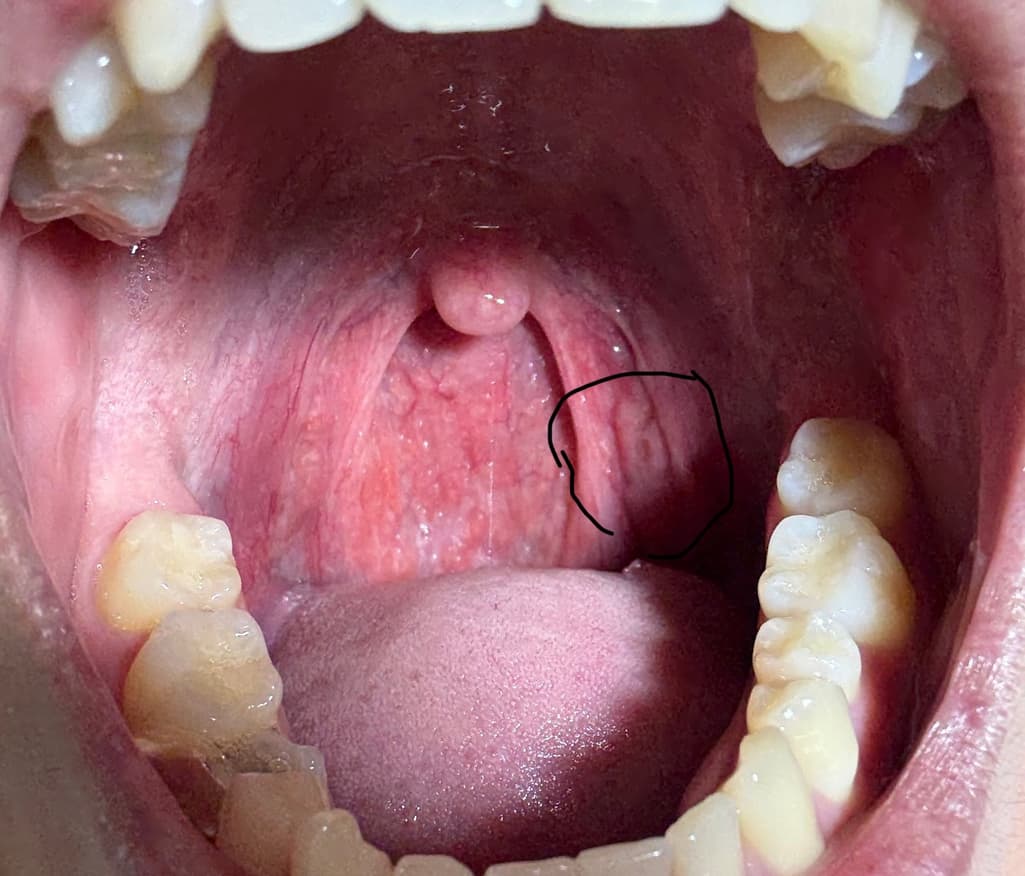

사진상 우측 편도부분 편도암 의심가는지 확인가능할까요

평소 편도가 자주 부어있고 편도염도 잦긴합니다. 하지만 사진상 우측에 있는 편도 부분이 비대칭처럼 육안상 부어있습니다.그리고 작은 여드름처럼 뭔가 있습니다.과거에는 이런적 없었고 비대칭처럼 된지 몇개월 지났습니다. 딱히 커지는지는 모르겠습니다만, 편도암 의심가는 양상일까요? 과거 이비인후과 내원했을때는 대충 보시더니 별거 아니라고 하셨습니다만, 문제있으면 다시 내원하려고합니다.

• 1번 째 사진

사진상 편도선으로 의심되는 부위의 점막의 불규칙한 표면 변화가 관찰되지만 편도암에서 관찰되는 종괴나 궤양성 병변이 아니므로 편도암으로 보기는 어렵습니다. 평소 편도염의 재발로 인한 만성 편도염이 발생하였고 이로 인한 편도 점막의 변화로 판단됩니다. 크기나 모양의 변화가 없다면 좀 더 지켜보아도 되겠으며 육안 소견상 편도암이 의심되는 것은 아니므로 당장 추가 검사나 진료를 필요하지 않겠습니다.